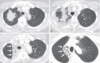

Fig. 3.1 Atelectasia obstructiva (reabsorbente) del lóbulo superior izquierdo por carcinoide endobronquial. Una tomografía computarizada con contraste muestra un tumor (flecha curvada) que obstruye el bronquio del lóbulo superior izquierdo con atelectasia completa del lóbulo superior izquierdo asociada (flechas rectas). Obsérvese el desplazamiento anterior y medial de la fisura principal izquierda (flechas rectas).